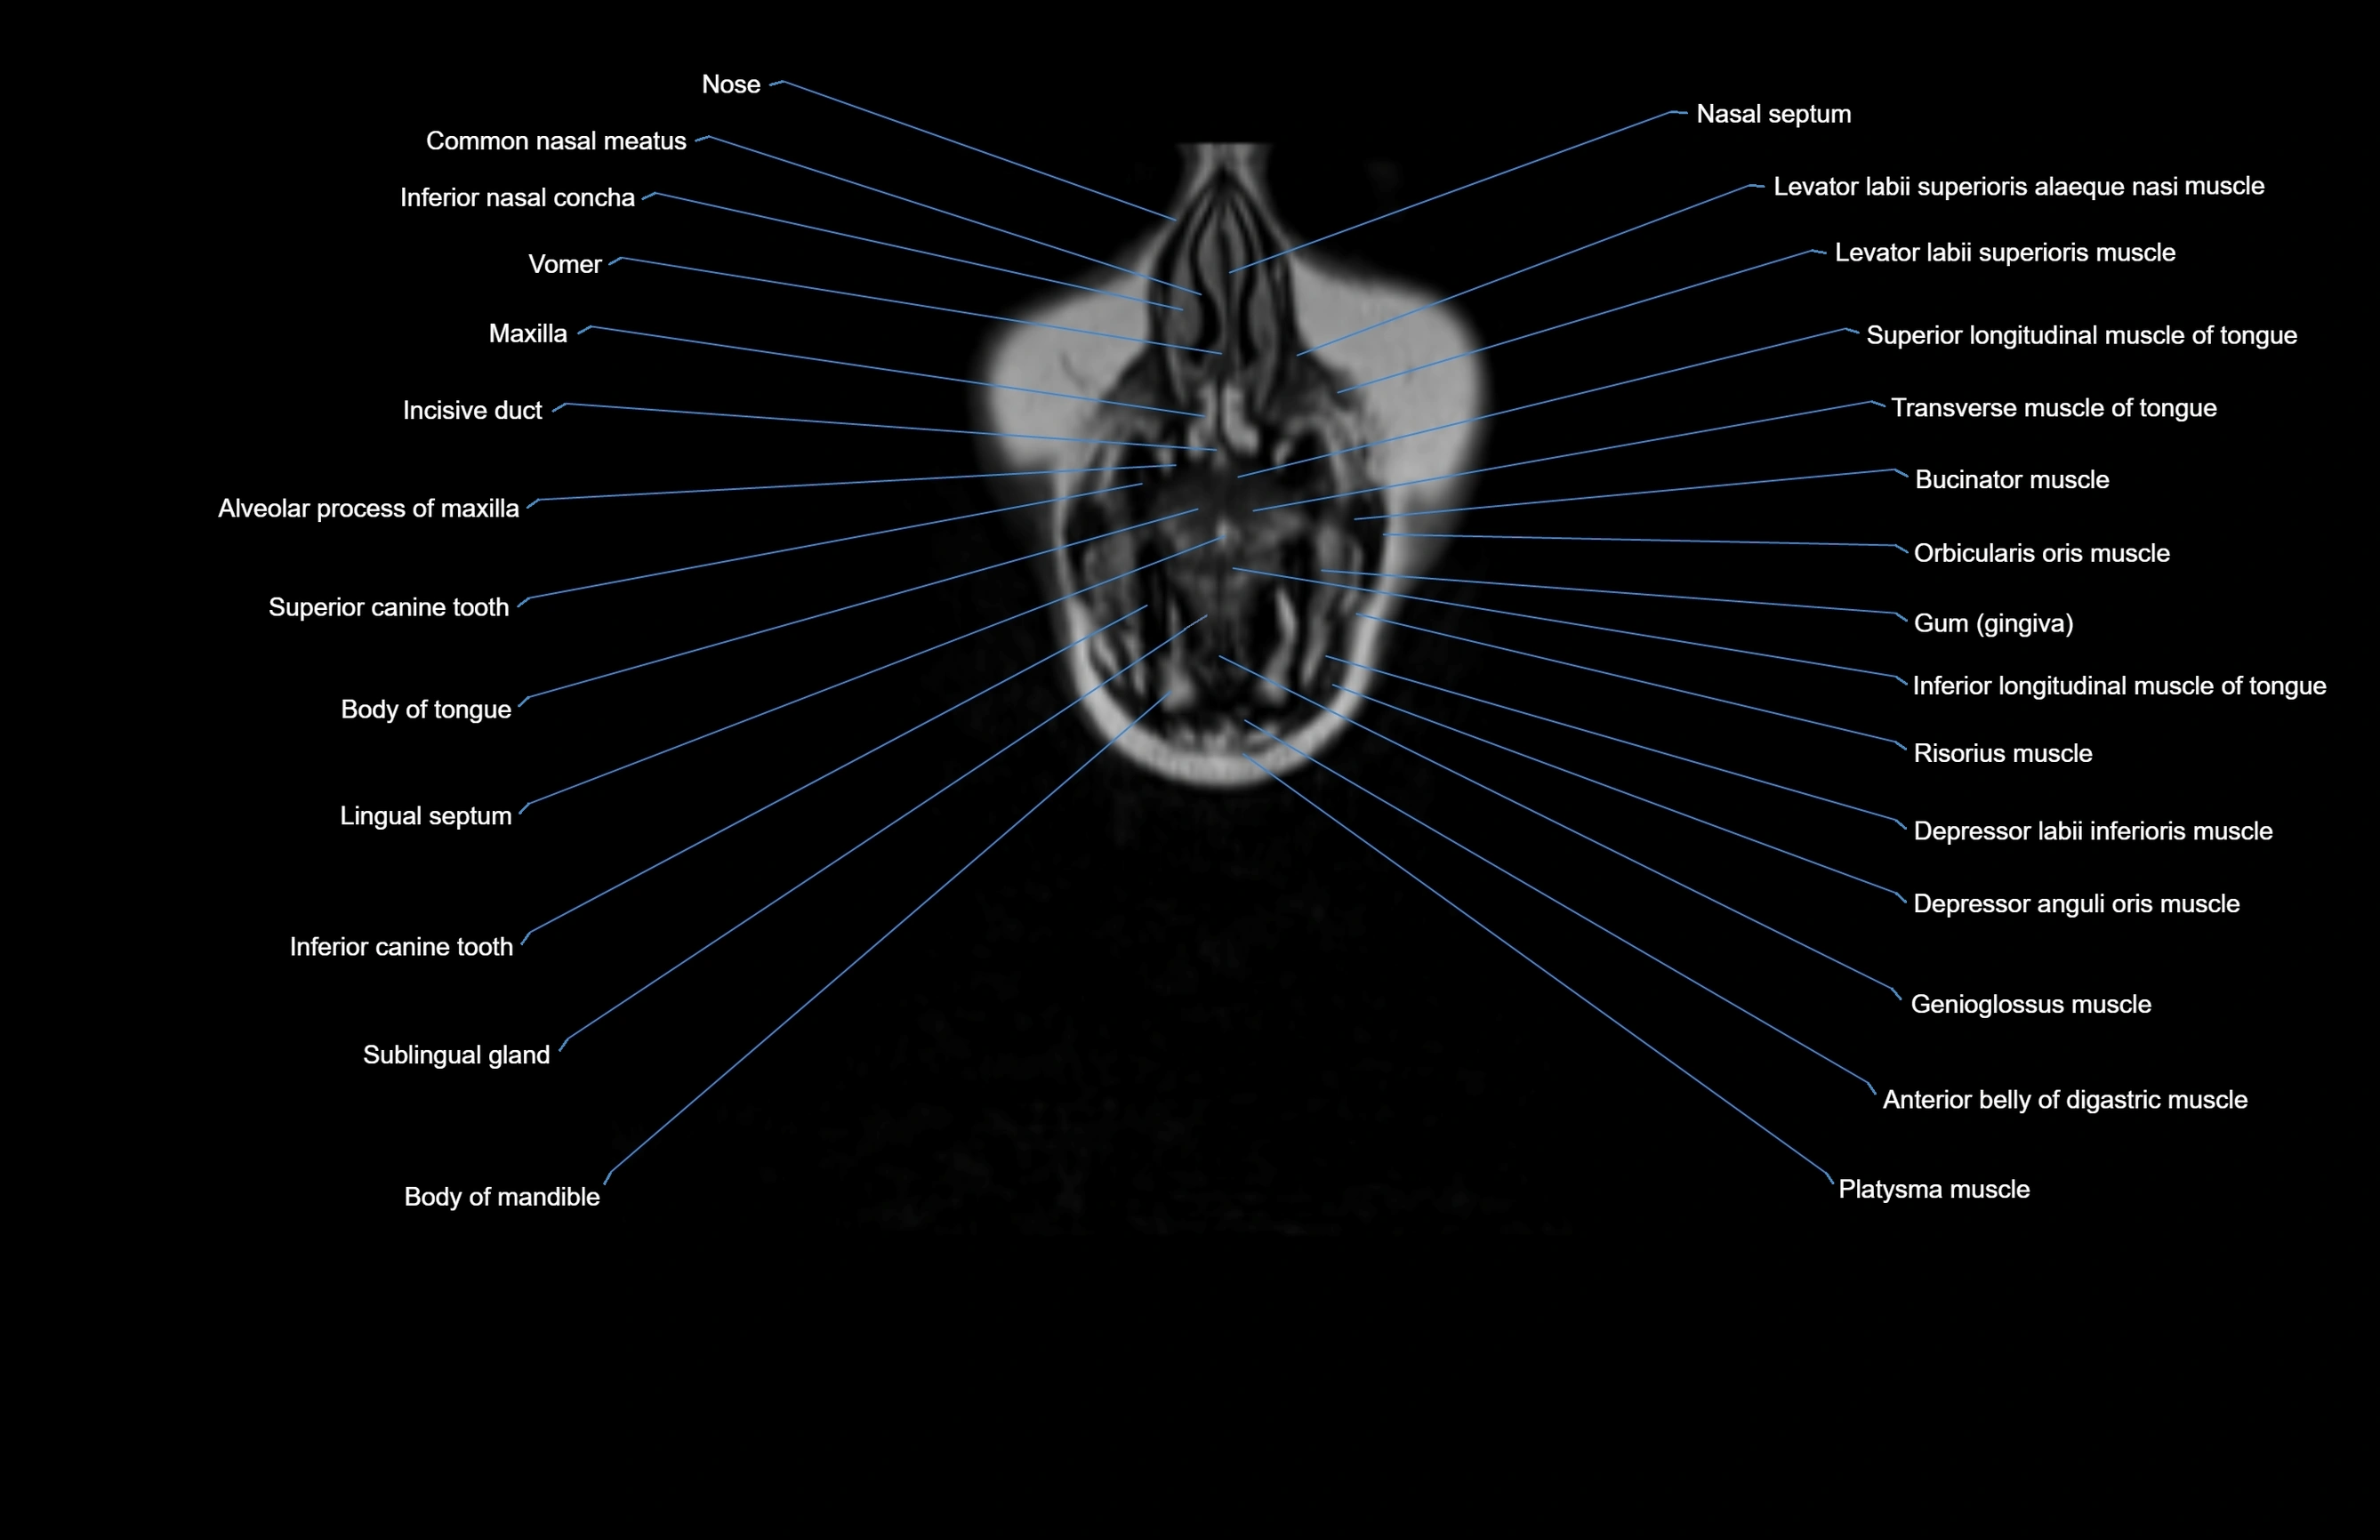

- Body of mandible

- Body of tongue

- Buccinator muscle

- Common nasal meatus

- Depressor anguli oris muscle

- Depressor labii inferioris muscle

- Depressor septi nasi muscle

- Genioglossus muscle

- Incisive duct

- Inferior canine tooth

- Inferior longitudinal muscle of tongue

- Inferior nasal concha

- Levator labii superioris alaeque nasi muscle

- Levator labii superioris muscle

- Lingual Septum

- Maxilla

- Nasal septum

- Orbicularis oris muscle

- Platysma muscle

- Risorius muscle

- Sublingual gland

- Superior longitudinal muscle of tongue

- Transverse muscle of the tongue